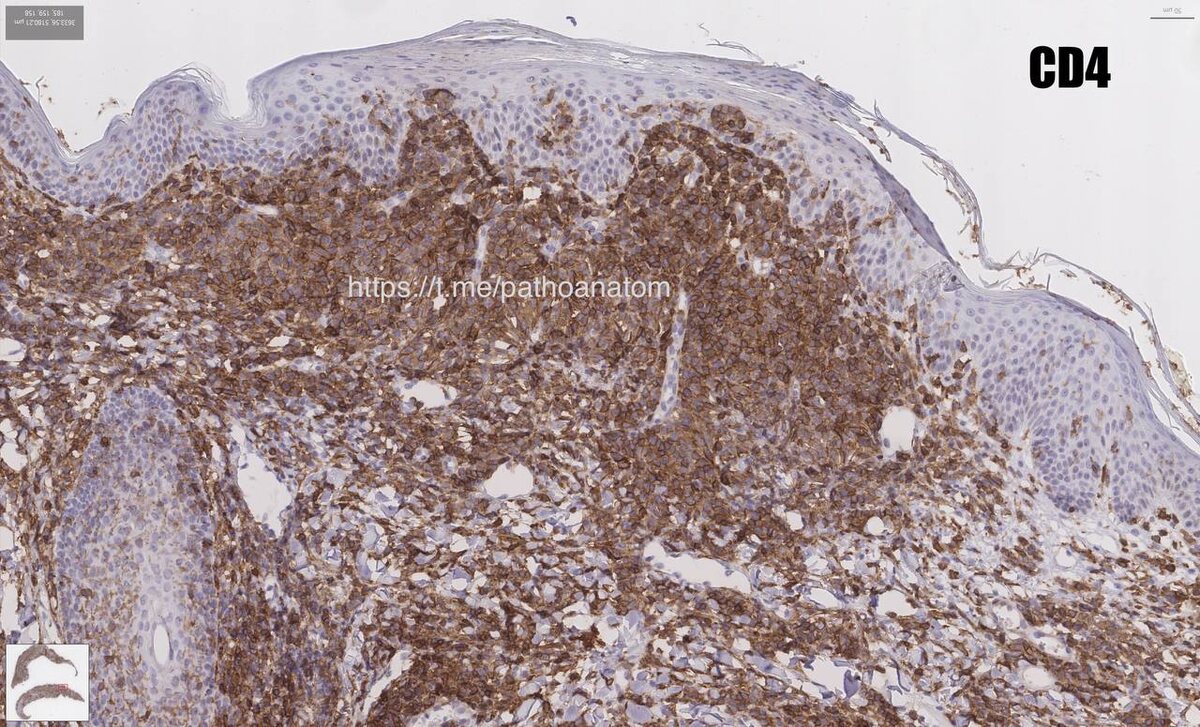

💉 Иммуногистохимические критерии:

1️⃣ Клетки инфильтрата состоят из T-хелперов – зрелых клеток памяти, которые имеют иммунофенотип: CD2+ CD3+ CD4+ CD5+ CD7+ CD8- CD45RO+

3️⃣ Увеличение соотношения CD4/CD8 (более чем 8/1) - хорошо видно на фото 🔝